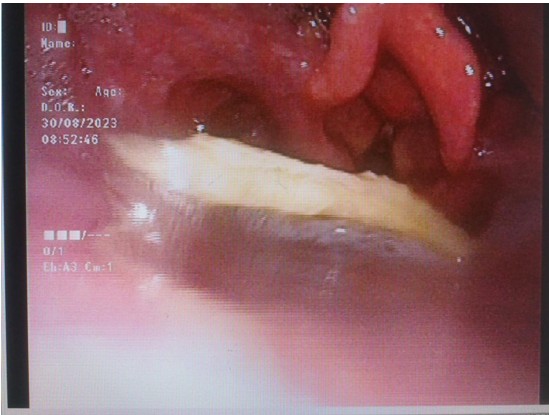

圖片一:電子鼻咽喉鏡顯示方形異物卡在喉咽部

面對(duì)困難,庾江東主任請(qǐng)來耳鼻咽喉頭頸外科主任醫(yī)師、副主任唐先龍,呼吸與危重癥醫(yī)學(xué)科副主任醫(yī)師羅勇飛,技師黃君。大家仔細(xì)研究卡住的鴿子骨頭,獻(xiàn)計(jì)獻(xiàn)策,不斷調(diào)整吸取設(shè)備,改善吸取方案,轉(zhuǎn)移診療室,在4位專家的合力支持配合下,經(jīng)過近2個(gè)小時(shí)的努力,終于在電子鼻咽喉鏡引導(dǎo)下,將一塊6x5㎝的鴿子骨頭從口腔取出來了!病人和家人都萬分感謝!